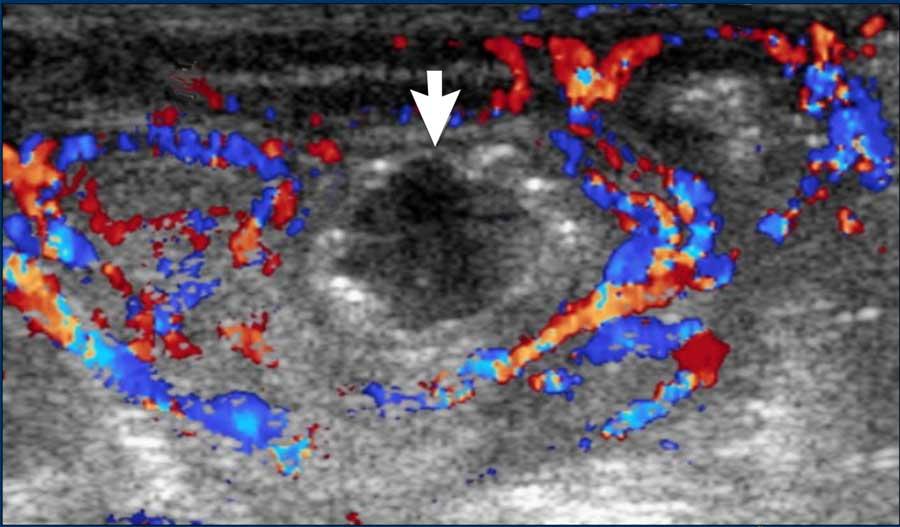

Doppler màu

Đánh giá thành ruột đòi hỏi một số kinh nghiệm.

Thành ruột bình thường có độ dày dưới 2,5 mm và có tín hiệu dòng chảy Doppler.

Thành ruột bệnh lý có biểu hiện dày lên (độ dày thành > 2,5 mm) và thành phù nề có tăng âm.

Có thể có tăng tín hiệu dòng chảy Doppler.

Điều này có thể khó đánh giá vì hầu hết trẻ sinh non bệnh nặng sẽ đang được hỗ trợ hô hấp và tín hiệu Doppler sẽ bị nhiễu bởi các xảo ảnh.

Trong bệnh tiến triển, khi ruột hoại tử hoàn toàn, thành ruột trở nên mỏng (độ dày thành < 1 mm) và không đều.

Tín hiệu dòng chảy Doppler sẽ giảm dần và cuối cùng mất hoàn toàn.

Hình ảnh

- Thành ruột bệnh lý: ruột dày và tăng âm, xen kẽ dịch cổ trướng.

- Thành ruột mỏng và không đều trong NEC tiến triển.

Hình ảnh Doppler cho thấy vắng mặt dòng chảy và sự hiện diện của khí trong thành ruột (pneumatosis intestinalis).

Hình ảnh được cung cấp bởi GS.TS. M Epelman, RadioGraphics 2007